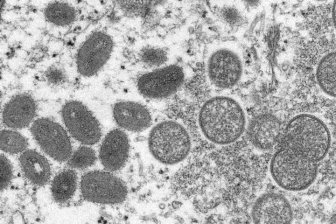

Monkeypox: Canada’s top doctor urges those at risk to get vaccinated as cases climbMonkeypox, which causes flu-like symptoms and skin lesions, is transmitted to humans from animals caused by an orthopoxvirus, which is related to smallpox, according to PHAC.CanadaJul 27, 2022

Hamilton records first case of rare monkeypox virus: public health'At this time the risk to the general public remains very low, as we have not detected the virus circulating in Hamilton, and the virus does not spread easily.'HealthJul 4, 2022